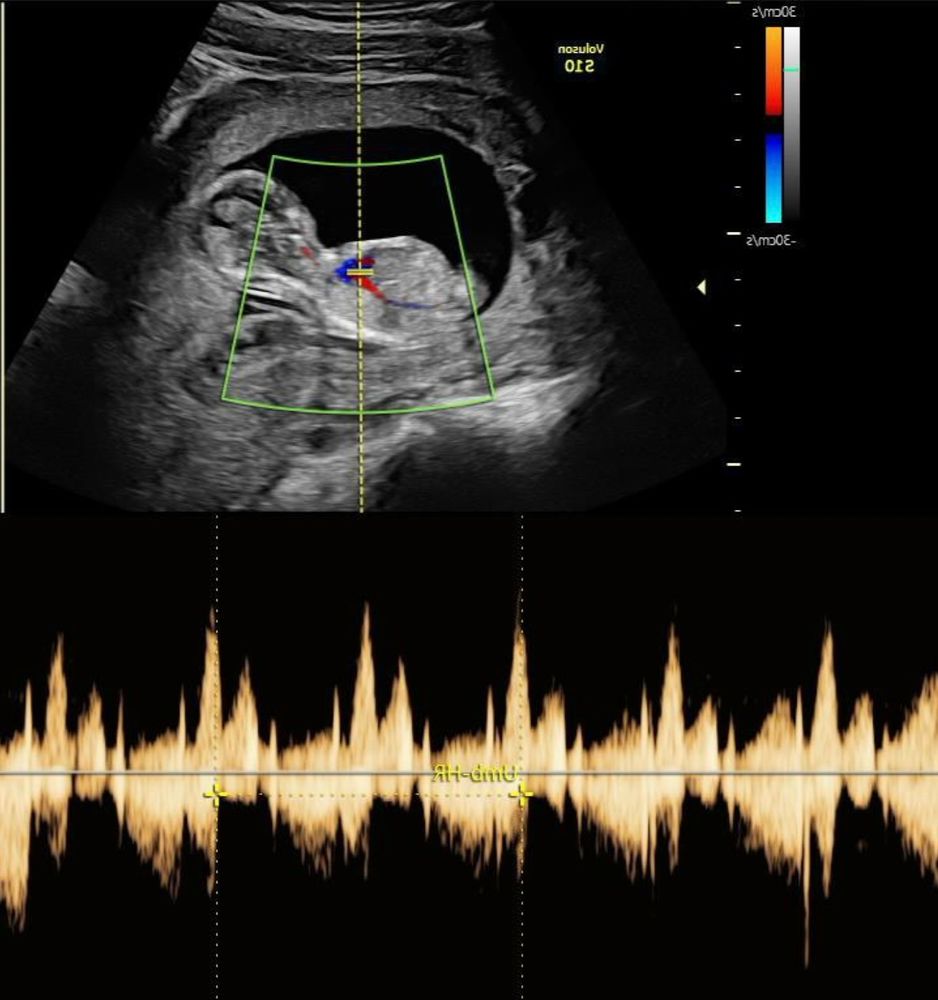

Получила фото из первого скрининга, на узи 11 недель сказали мальчик, в 13 - девочка. Как думаете, кто у нас?

Мальчик будто по половому бугорку

Ну пол ребёнка определяют абсолютно с другого ракурса, вы ведь сами видите что ребёнок лежит боком. Да и срок у вас маловат для точного определения пола. Подождите хотя бы 16 недель, ну или как вариант кровь, если не терпится. Мне лично в 20 сказали, на втором скрининге. Тоже конечно руки чесались раньше узнать, но мне узист сказал нечего бегать, на втором скрининге точно узнаешь.